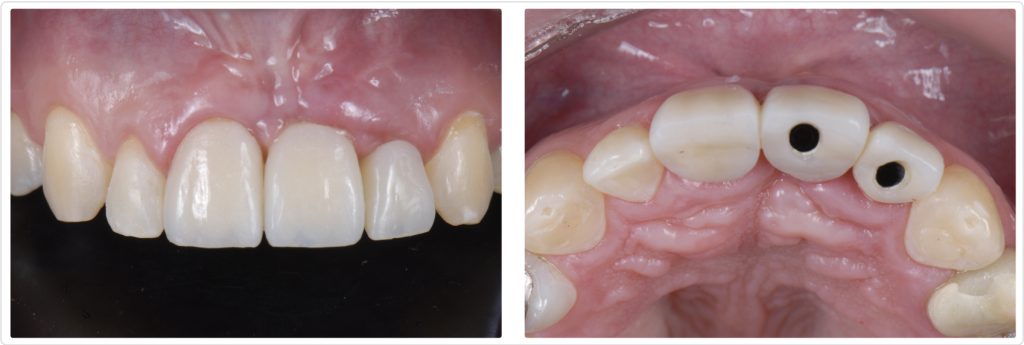

Several elements of his previous treatment (Figs. 1–5) were visibly deficient:

- The restoration was ill-fitting, and tartar and plaque had accumulated at the implant interface.

- The implant was placed too far apical and facial, creating an asymmetric gingival level when viewed alongside the adjacent central incisor. (When working with central incisors, care must be taken to provide gingival symmetry to attain an esthetic outcome, and this was far from it.)